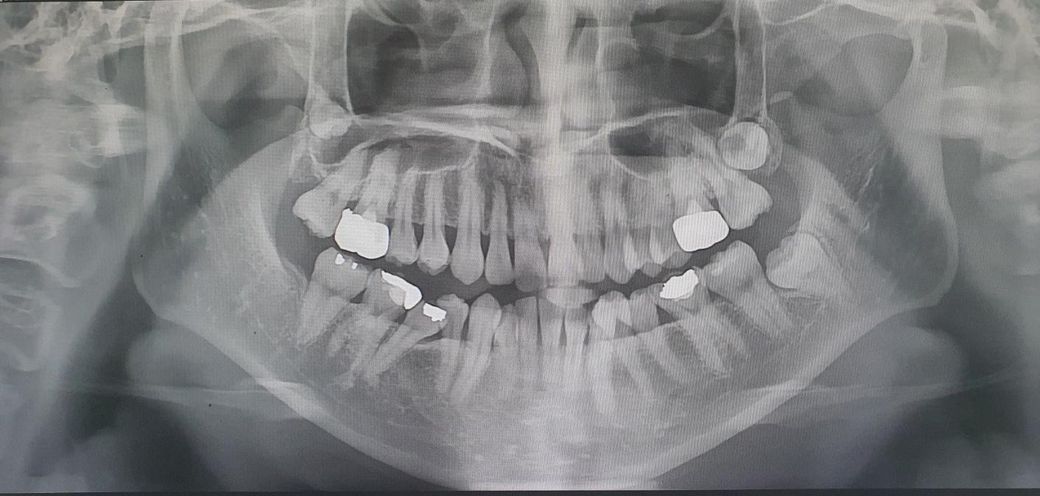

파노라마 사진으로 보이는 양쪽 턱뼈 길이 차이

치과치료 갔다가 파노라마 사진을 찍었는데

양쪽 턱뼈 길이 차이가 많이 나서 보고 놀랬어요....

비대칭이 있는데 저거때문인거죠? 양악해야지만

비대칭을 맞출 수 있는걸까요

인체는 애초에 대칭적이지 않으며, 어느 정도의 비대칭은 자연스럽게 있을 수 있습니다. 올리신 사진을 통해서 심하다고 볼 정도로 비대칭이 있는지는 잘 모르겠습니다. 관련하여서는 보다 정확한 감별을 위해서는 파노라마 사진만으로는 부족할 수 있으며 3D CT 등 보다 정밀한 검사가 필요할 수 있습니다. 확실하게 심한 비대칭이 있다고 결론이 난다면 교정과 관련하여서는 양악 수술이 고려될 수 있는 것은 맞겠습니다.